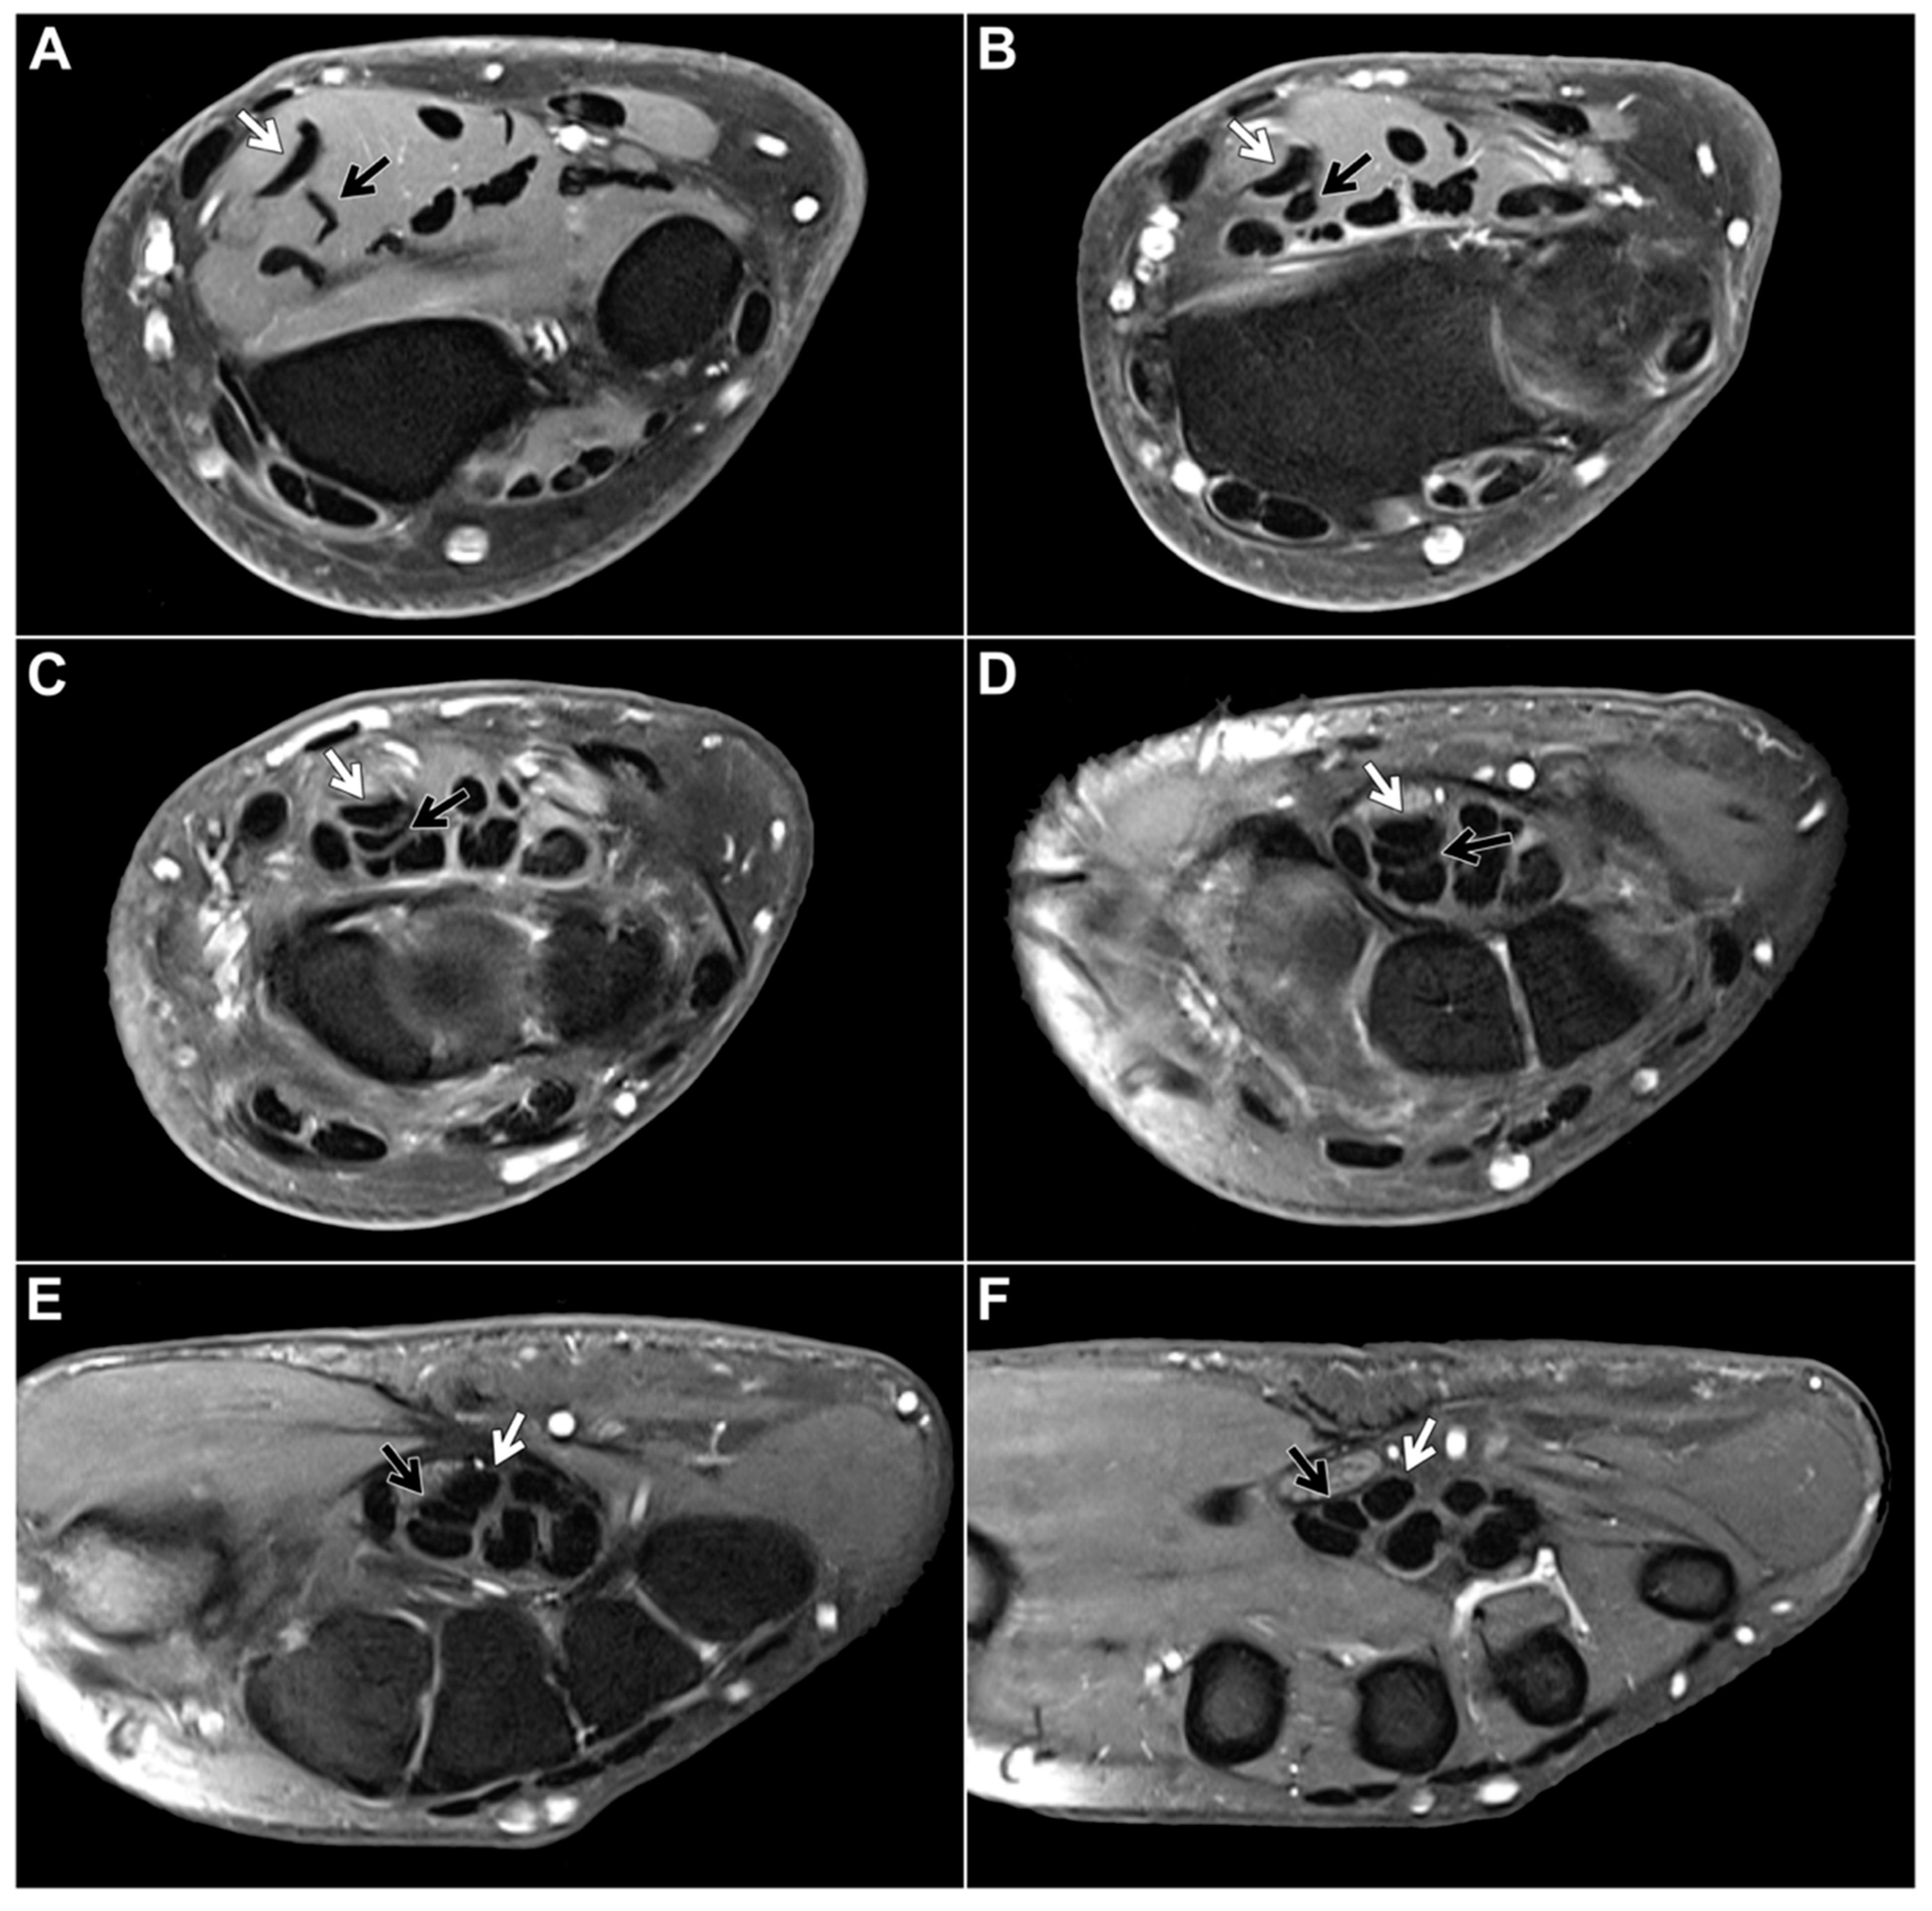

Within the study sample, the chiasma antebrachii with the above-described anatomical features was identified in 88 patients (98.9%). We defined the proximal margin of the chiasma as the first axial slice where the distal FDS/2 tendon was depicted inferiorly to the FDS/3 tendon and the distal margin as the first axial slice when the two tendons could be depicted horizontally adjacent to each other again (Figure 2). Measured according to these parameters, the chiasma antebrachii had a median length of 28 mm (IQR: 24 mm–35 mm). Next, we assessed the location of the chiasma in the forearm in relation to the distal radioulnar joint and the elbow joint. We measured the respective distance from the proximal margin and documented a median distance to the distal radioulnar joint of 16 mm (IQR: 8 mm–25 mm) and a median distance to the elbow joint of 215 mm (IQR: 187 mm–227 mm). Measurements were performed based on axial images but were correlated in at least one other standard plane. In only one patient, the intersection was located in the middle part of the forearm. In this particular case, the intermediate tendon of the FDS crossed under the FDS3 from the ulnar to the radial side. As a consequence, the distal FDS tendon segments for digits 2 and 3 could be depicted running parallel to each other in the distal third of the forearm up to their insertions at the mid phalanx of digits 2 and 3, with the FDS/2 located more radially (Figure 3).

Figure 3. Contrast-enhanced, fat-suppressed T1-weighted turbo spin echo in a 44-year-old woman for presumed inflammatory disease of the right forearm depicts an anatomical variant of FDS anatomy without a typical (distal) chiasma antebrachii. Instead of an intersection, the distal FDS/2 (black arrow) and FDS/3 (white arrow) tendons run parallel to each other ((A,B): forearm level, (CE): carpal tunnel level, (F): midcarpal level).